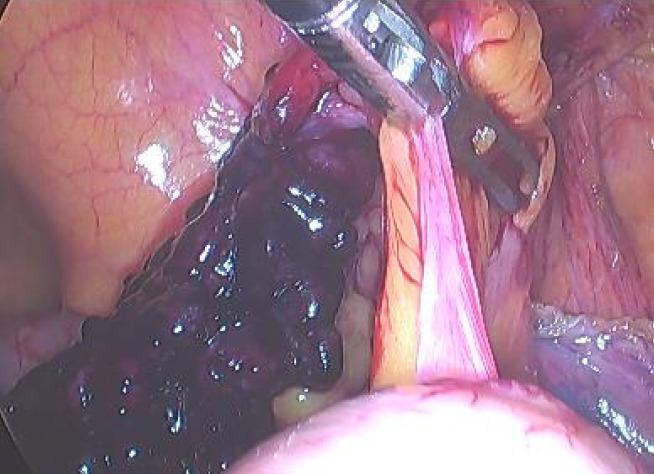

A 59-year-old man was admitted to the hospital with a painful right inguinal mass that had suddenly developed 6 hours earlier. Physical examination revealed a 4 cm × 2 cm palpable mass in the right groin. The mass was hard and could not be reduced due to tenderness. It did not descend into the scrotum. B-ultrasound revealed an incarcerated hernia. During surgery, the hernia was found to contain the appendix, which exhibited distal avascular necrosis. A De Garengeot hernia was diagnosed according to the classification criteria of this type of inguinal hernia. Laparoscopic reduction of the incarcerated hernia, appendectomy, and small-incision femoral hernia repair were performed in the emergency department, and cefuroxime was administered as anti-infection therapy for 2 d postoperatively. After treatment, the patient had no abdominal pain or infection and was discharged on postoperative day 4. He had no recurrence of the inguinal hernia after 16 months of follow-up.

一名59岁男性因6小时前突然出现的右侧腹股沟疼痛性肿块入院。体格检查发现右侧腹股沟可触及一个4 cm×2 cm的肿块。肿块质地硬,因压痛无法还纳。未降入阴囊。B超显示为嵌顿疝。手术中发现疝内容物包含阑尾,阑尾表现为远端缺血坏死。根据此类腹股沟疝的分类标准诊断为德加伦若疝。在急诊科进行了腹腔镜下嵌顿疝还纳、阑尾切除术及小切口股疝修补术,并在术后给予头孢呋辛抗感染治疗2天。治疗后,患者无腹痛及感染,术后第4天出院。随访16个月,腹股沟疝未复发。